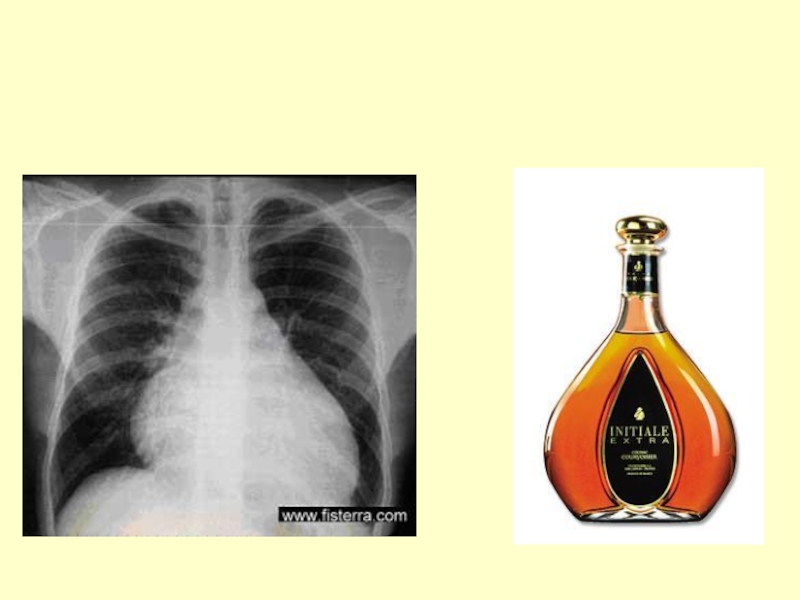

Слайд 46Pентгенограмма грудной клетки больной O.

Pентгенограмма грудной клетки больной O.

Слайд 79Больная О., 58 лет

Больная О., 58 лет